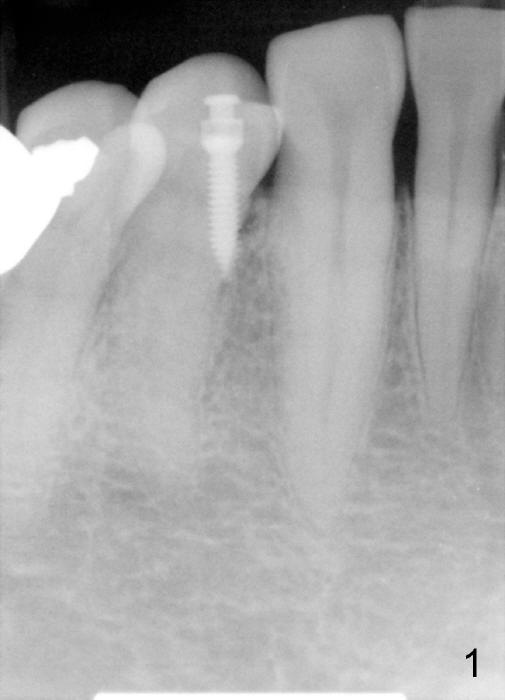

A 1.6x6 mm mini-implant was placed between #27 and 28 on 02/20/2014 (Fig.1,2). The major problem is its angulation. A 1/4 elastic cannot be placed over it. Instead a ligature wire is used to hold the elastic in place (Fig.3,4, taken 2 months later). Occlusal reduction is done (Fig.4), which alleviates the discomfort. But the extrusion is not obvious, since retraction is not 24 hours. The elastic and wire needs replacement quite often, which is not patient friendly. The extraoral Bitewing is taken 2.5 months post implantation (Fig.5). The tooth #6 has a long root. What should we do?